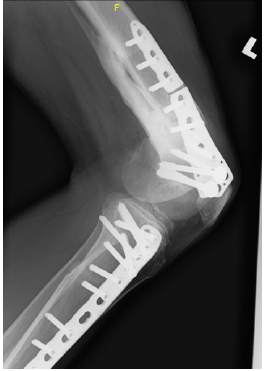

White blood cell count and C- reactive protein was not elevated with the reading of 3.8x109/L and 0.5 mg/dL respectively. Erythrocyte sedimentation rate was slightly elevated at 30mm/hr. His lower limb radiograph reveals a broken implant and atrophic non- union of his distal femur with thirty degrees medial angulation (Figure 1). There was no significant antero- posterior angulation or translation (Figure 2). The radiograph was not suggestive of any long-standing infective process or osteomyelitis.

Figure 1: Full length antero- posterior plain radiograph reveals a broken implant, atrophic non- union of left distal femur with thirty degrees medial angulation.